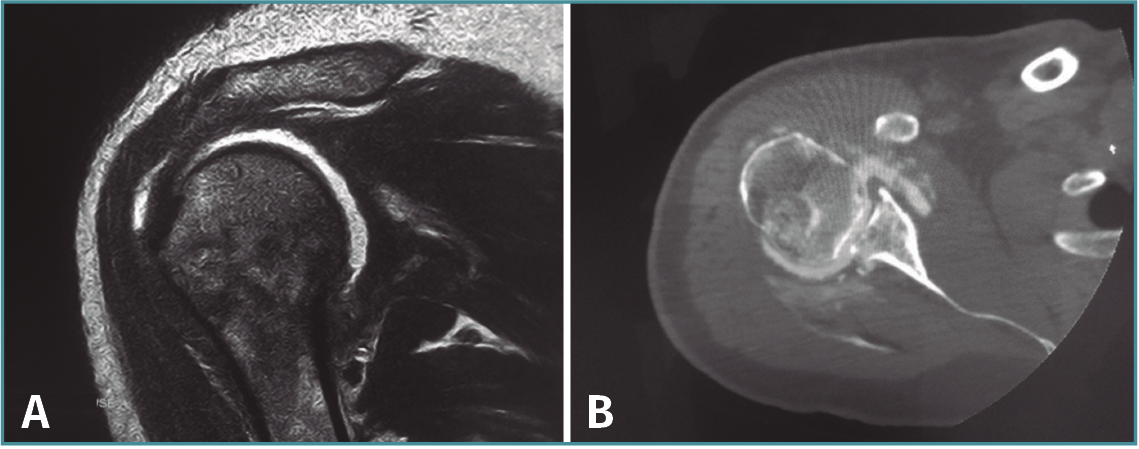

El postoperatorio transcurre sin incidencias, comprobándose la correcta congruencia articular en la resonancia magnética (RM) a las 4 semanas de la cirugía y en la artro-TC de control a los 2 meses de la misma (Figura 3). Tras la cirugía se mantiene inmovilización con cabestrillo durante 4 semanas, iniciándose el tratamiento físico rehabilitador mediante ejercicios pasivos y asistidos a la tercera semana, ejercicios activos a las 6 semanas y fortalecimiento muscular a los 3 meses.

Figura 3. Corte coronal de resonancia magnética (A) y corte axial de artrotomografía computarizada (B) postoperatorios en los que se observa la reducción de la cabeza humeral en la glena sin otras lesiones asociadas.